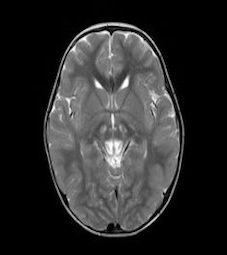

Brain Tumor MRI dataset:

The Brain Tumor MRI Images dataset is a publicly available dataset on Kaggle555https://www.kaggle.com/datasets/sartajbhuvaji/brain-tumor-classification-mri/data. It contains MRI images of human brains divided into four categories: No Tumor, Pituitary Tumor, Benign Tumor, and Malignant Tumor. For our study, we selected three categories: No Tumor (NT), Benign Tumor (BT), and Malignant Tumor (MT). From each category, we chose three MRI images representing different parts of the brain that best illustrate the characteristics of each class. The categories included in this study are described as follows:

The No Tumor (NT) category contains MRI images of healthy brains with no abnormal growths or masses. In these images, the brain tissue appears normal, and there are no signs of tumors or unusual structures. These images serve as a baseline, allowing for effective comparison and detection of abnormalities in other MRI scans.

Refer to caption

(a) NT1

(b) NT2

(c) NT3

(d) BT1

(e) BT2

(f) BT3

(g) MT1

(h) MT2

(i) MT3

Figure 5. Axial and Coronal MRI Images of Brains Representing Different Tumor Categories

The Benign Tumor (BT) category includes MRI images showing non-cancerous tumors in the brain. Benign tumors grow slowly and do not spread to other parts of the brain or body. While generally less dangerous than malignant tumors, they can still cause symptoms if they press on surrounding brain tissue. Accurate identification of benign tumors is important for planning appropriate treatment, which may involve monitoring, minor surgery, or other non-aggressive interventions.

The Malignant Tumor (MT) category consists of MRI images showing cancerous tumors. These tumors are aggressive, can grow rapidly, and may spread to other parts of the brain or body. Malignant tumors require immediate and intensive treatment, such as surgery, chemotherapy, or radiotherapy. Differentiating malignant tumors from benign tumors is crucial, as it directly impacts the treatment strategy and can significantly affect patient outcomes.

Differentiating these categories is essential for early detection, accurate diagnosis, and effective treatment planning. By distinguishing between healthy brains, benign tumors, and malignant tumors, medical professionals can identify abnormalities more reliably, reduce misdiagnoses, and streamline medical care. In this study, we apply our divergence measure to differentiate between the selected MRI images, as illustrated in Figure 5. In Figure 5, the first row shows MRI images from NT patients, the second row shows images from BT patients, and the third row shows images from MT patients.

Using the divergence measure, we calculated estimates for each pair of MRI images and compared the three categories. For calculation, each grayscale image is represented by its pixel intensity values (scaled to [0,1]). These values are flattened into a one dimensional vector and used as the sample data for subsequent analysis. For any two images, denoted data1 and data2, we then computed an empirical based divergence estimate. The resulting values are presented in Tables 4, 5, and 6. A higher value of the divergence estimate indicates a greater likelihood of a tumor. These results demonstrate that the divergence measure can serve as an effective tool for detecting tumors in medical image data.

While our study demonstrates the effectiveness of the divergence measure in differentiating brain MRI images across tumor categories, the results could be further strengthened with longitudinal data, where MRI scans of the same individuals are available at different stages of tumor progression, captured with consistent size and image quality. The current dataset, being cross-sectional, limits the ability to draw more definitive conclusions regarding tumor evolution. Incorporating longitudinal data in future studies would provide deeper insights and allow for more robust validation of the divergence measure in tracking disease progression.